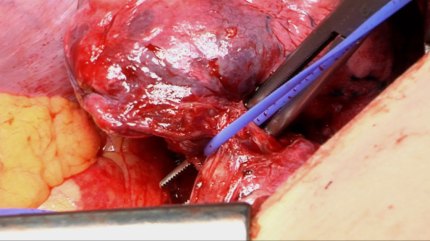

This is a video still from a lung cancer operation (lobectomy) where the light was positioned in a way that provided good light but bad framing. Approximately 50 % of the footage from this operation was framed similar to this.